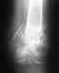

По заключениям к анализам(КТ, МРТ, Рентген) пишут артроз , кэм-импиджмент, киста левого тбс.Скажите пожалуйста, что возможно сделать в данной ситуации чтобы избежать ендопротезирования тбс и остаться физически активным.

КТ:

https://transfiles.ru/qz1u5

МРТ и Рентген:

https://transfiles.ru/s8o4k

• Кликните для загрузки файла 1.jpg